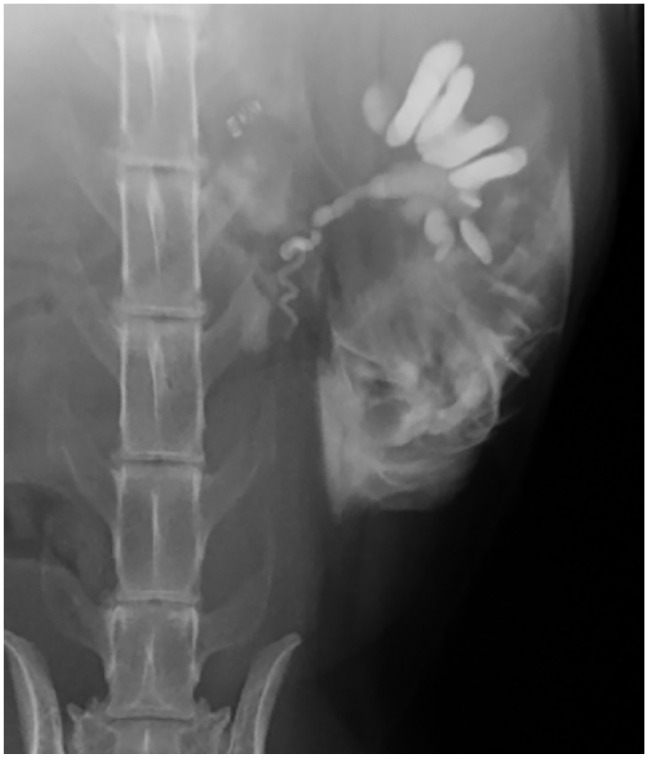

病例摘要:患者是一只 5.5 岁的雄性阉割短毛猫,两年前开始出现进行性慢性肾病。腹部超声波检查发现双侧慢性肾脏变性、肾结石、皮质高回声和梗死。使用 Synovis 血管耦合系统对肾动脉和静脉进行端对端吻合,进行了左侧正位肾移植。移植两个月后,肾脏数值升高,腹部超声波检查发现移植肾肾积水和肾积脓。透视前行肾盂造影发现近端输尿管狭窄。对其进行了近端新输尿管囊肿切除术,术后肾脏数值恢复正常。12 个月后,该猫因急性绞窄尿和严重氮质血症接受了重新评估。对比增强 CT 显示移植肾出现严重肾积水,近端输尿管阻塞,膀胱粘连。经探查发现,腹膜后纤维化覆盖了移植肾。考虑到临床情况,患者被放置了皮下输尿管旁路装置(SUB)。每隔 1-3 个月对临床病理分析、环孢素谷值、需氧尿培养和移植肾的超声波评估进行一次监测。每 3-6 个月重新评估一次 SUB 的通畅性。放置 SUB 15 个月后,由于膀胱造口导管扭结,SUB 出现闭塞,因此进行了更换。放置 SUB 后 28 个月,该猫的肾功能和临床状况恶化,最终安乐死:据作者所知,这是首次报道使用 SUB 装置治疗猫移植肾的输尿管梗阻。

Case summary: A 5.5-year-old male neutered domestic shorthair cat was presented with a 2-year history of progressive chronic kidney disease. Abdominal ultrasonography revealed bilateral chronic renal degeneration, nephrolithiasis, cortical hyperechogenicity and infarction. Left orthotopic renal transplantation was performed using the Synovis vascular coupling system for end-to-end anastomosis of the renal arteries and veins. Two months after transplantation, renal values were elevated, and abdominal ultrasonography revealed hydronephrosis and hydroureter of the transplanted kidney. Fluoroscopic antegrade pyelography identified a proximal ureteral stricture. Proximal neoureterocystostomy was performed and renal values normalized postoperatively. The cat was re-evaluated for acute stranguria and severe azotemia 12 months later. Contrast-enhanced CT revealed severe hydronephrosis of the transplanted kidney, obstruction of the proximal ureter and adhesions to the urinary bladder. Upon exploration, retroperitoneal fibrosis was found covering the transplanted kidney. Given the clinical situation, a subcutaneous ureteral bypass device (SUB) was placed. Clinicopathologic analyses, trough cyclosporine levels, aerobic urine cultures and ultrasonographic evaluations of the transplanted kidney were monitored every 1-3 months. Patency of the SUB was reassessed every 3-6 months. At 15 months after placement, the SUB occluded due to kinking of the cystostomy catheter and was replaced. At 28 months after SUB placement, renal function and clinical status deteriorated, and the cat was euthanized.